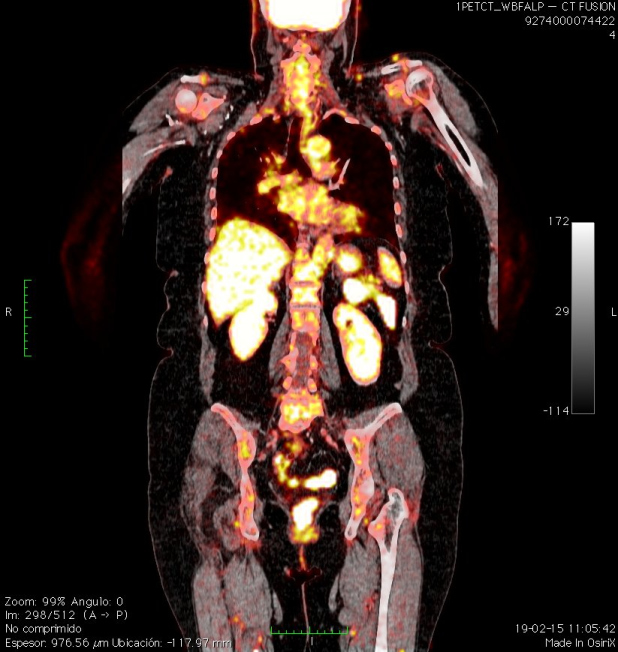

Se realiza PET-CT de etapificación con 18F-FDG, donde se observa un nódulo subcutáneo sólido de 11 mm, bien delimitado, condensidad de partes blandas, ubicado en hombro izquierdo adyacente a la articulación acromioclavicular. Se evidencia aumento del metabolismo glucídico (SUVmax = 3,2) (Fig. 2) y una adenopatía supraclavicular ipsilateral de 15 mm, hipermetabólica (SUVmax = 3.5) (Fig. 3). El resto de la exploración no mostró lesiones hipermetabólicas (Fig. 4).